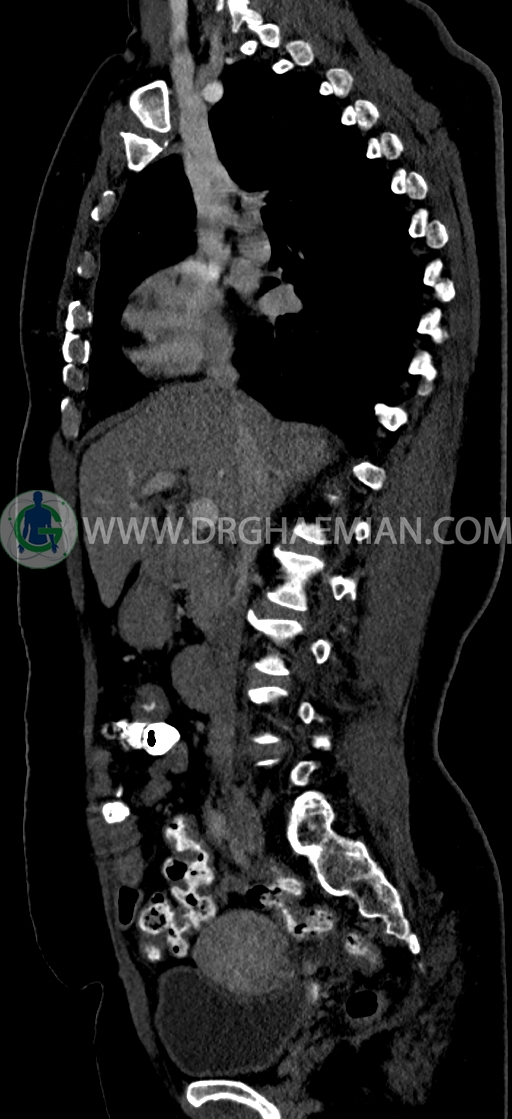

در سي تي اسکن اسپيرال ريه و مدياستن-شکم و لگن با کنتراست خوراکی و وريدی (مولتي ديدکتور 16 با مقاطع ظريف و بازسازي هاي ساژيتال و کرونال) :

-فيبروم اينترامورال- ساب سروزال به سايز 35mm در قدام فوندوس با اثر فشاري بر ديواره فوقاني مثانه

–Bridging osteophyte در مهره هاي توراسيک مطرح کننده DISH همراه با کيفوز مشهود است.

-هرني سوپرا امبليکال با ديفکت به سايز 10mm حاوي چربي و هرني امبليکال با ديفکت به سايز 7mm حاوي چربي مشهود است.